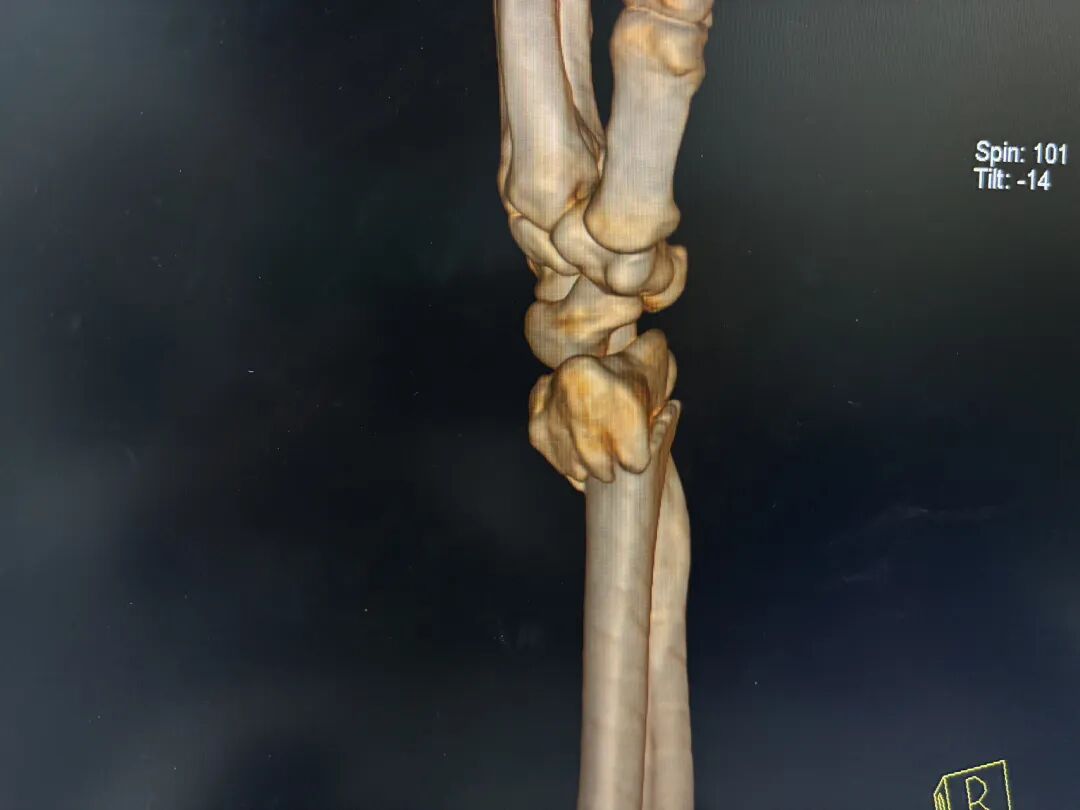

典型克雷氏外观:骨折远端向背侧移位,导致腕关节侧面呈现类似“餐叉”的畸形,即骨折端向背侧突出,形成明显的成角畸形。

这种相互嵌插的克雷氏骨折最容易造成上述复位后残留掌侧角度的问题。

其根本原因在于,牵引复位中直接掌倾只纠正了背侧嵌插。